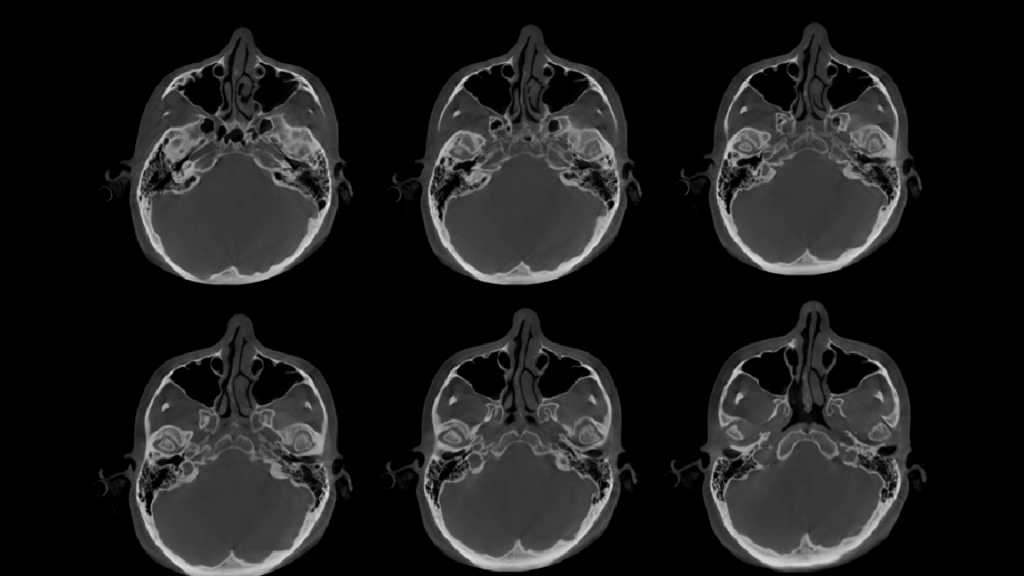

A la evaluación de la tomografía computarizada de haz cónico (FOV 10 X 10) se observa que ambos cóndilos presentan un aplanamiento marcado de los contornos, erosión de las corticales, así como la presencia de osteofitos. Asimismo, se observa el aplanamiento de la cavidad glenoidea bilateral y la disminución considerable de los espacios articulares. Finalmente, en la tomografía de boca abierta y cerrada se observa la disminución en el recorrido condilar bilateral, signos imagenológicos compatible con proceso degenerativo articular e hipomovilidad bilateral.

CORTES AXIALES

CORTES CORONALES Y SAGITALES